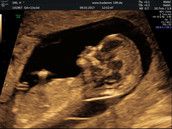

Die Anzeichen für eine SS habe ich die ganze Zeit und heute Test = Positiv

4+0